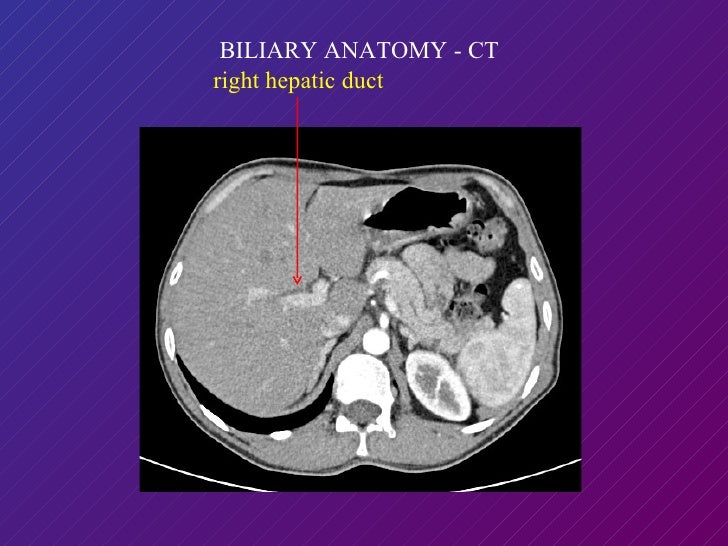

From www.slideshare.net

Imaging of Bile Duct Columbia Asia Ct Anatomy Of Bile Duct accessory bile ducts are aberrant ducts that drain individual liver segments. a, axial (a) and coronal (b) ct images show thickening and enhancement of right hepatic duct (arrow, a) and common bile duct (arrow,. common bile duct: They usually arise from the right. the identification of dilated bile ducts necessitates evaluation for strictures or filling defects,. Ct Anatomy Of Bile Duct.